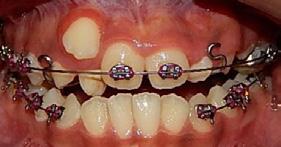

de microtornillos en la cresta Infracigomática (IZC) 2 × 14 mm con cadena hacia los OD 13 y 24; se utilizó doble arco con bypass para incorporar el OD 13 el arco principal era de SS 0.018 y el accesorio NiTi 0.012, para obtener clase I molar bilateral se usaron elásticos intermaxilares clase II; mientras que se realizó distalización superior con anclaje máximo y cadena intramaxilar 3/16 4.5 oz para la clase I canina bilateral; para la corrección del overjet y overbite se hizo distalización mandibular y posterior maxilar con control de torque superior e inferior con cadena de torque.

En la coincidencia de las líneas medias con la distalización al microtornillo en IZC, manejo de espacio con stripping, alineación y nivelación; la máxima intercuspidación, paralelismo radicular y oclusión funcional se llevó a cabo con el detallado con arco SS 0.017 × 0.025 y 0.019 × 0.025 superior e inferior, dobleces de primer orden (offset de OD 13,43), segundo orden (extrusión de OD 26, Tip distal de OD 13, 23 y 33) y elásticos clase II en caja bilateral 3/16 6.5 oz; (Figura 7). Para la estabilidad y postratamiento se recomendó un retenedor circunferencial superior e inferior con fijo de 12 a 22 y de 33 a 43.

Dentista y Paciente 44 Caso clínico

Figura 7. Progreso lateral derecho e izquierdo. Figura 8. Extraoral frente sonrisa perfil final. Figura 9. Intraoral frente inicio, final y lado izquierdo.